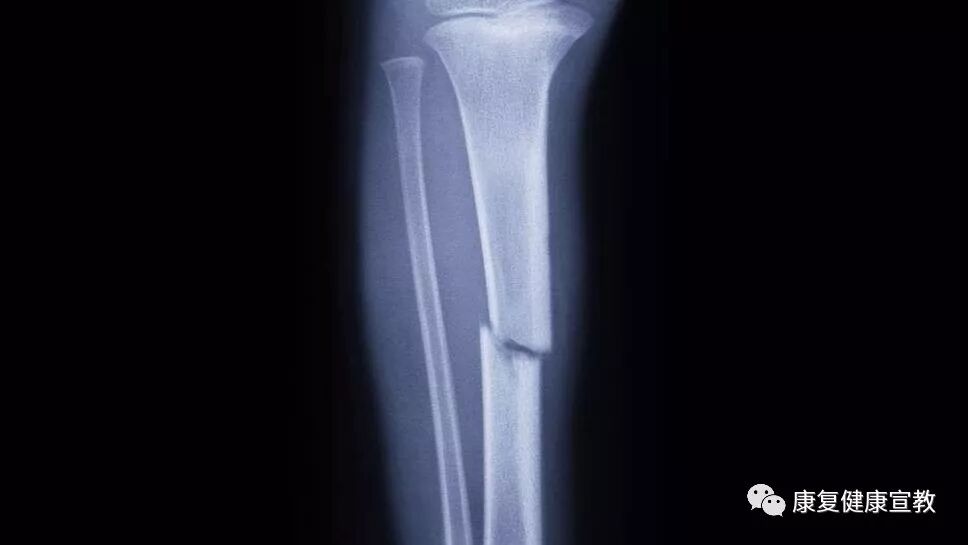

胫腓骨骨折术后的康复训练 康复健康宣教 微信公众号文章阅读 Wemp

胫腓骨骨折的术后康复方案 需要的自取 快资讯